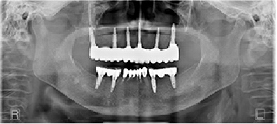

症例集

症 例

01

骨造成と歯肉移植併用

50歳・男性

骨造成と歯肉移植を併用してインプラントを埋入することで審美的に仕上げることができました。

02

骨造成と抜歯即時

70歳・女性

抜歯した直後にインプラントを埋入しさらに歯肉を移植することで審美的に仕上げることができました。